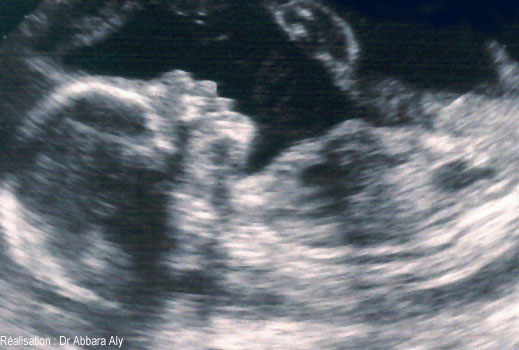

Profil foetal à 23 semaines d'aménorrhée